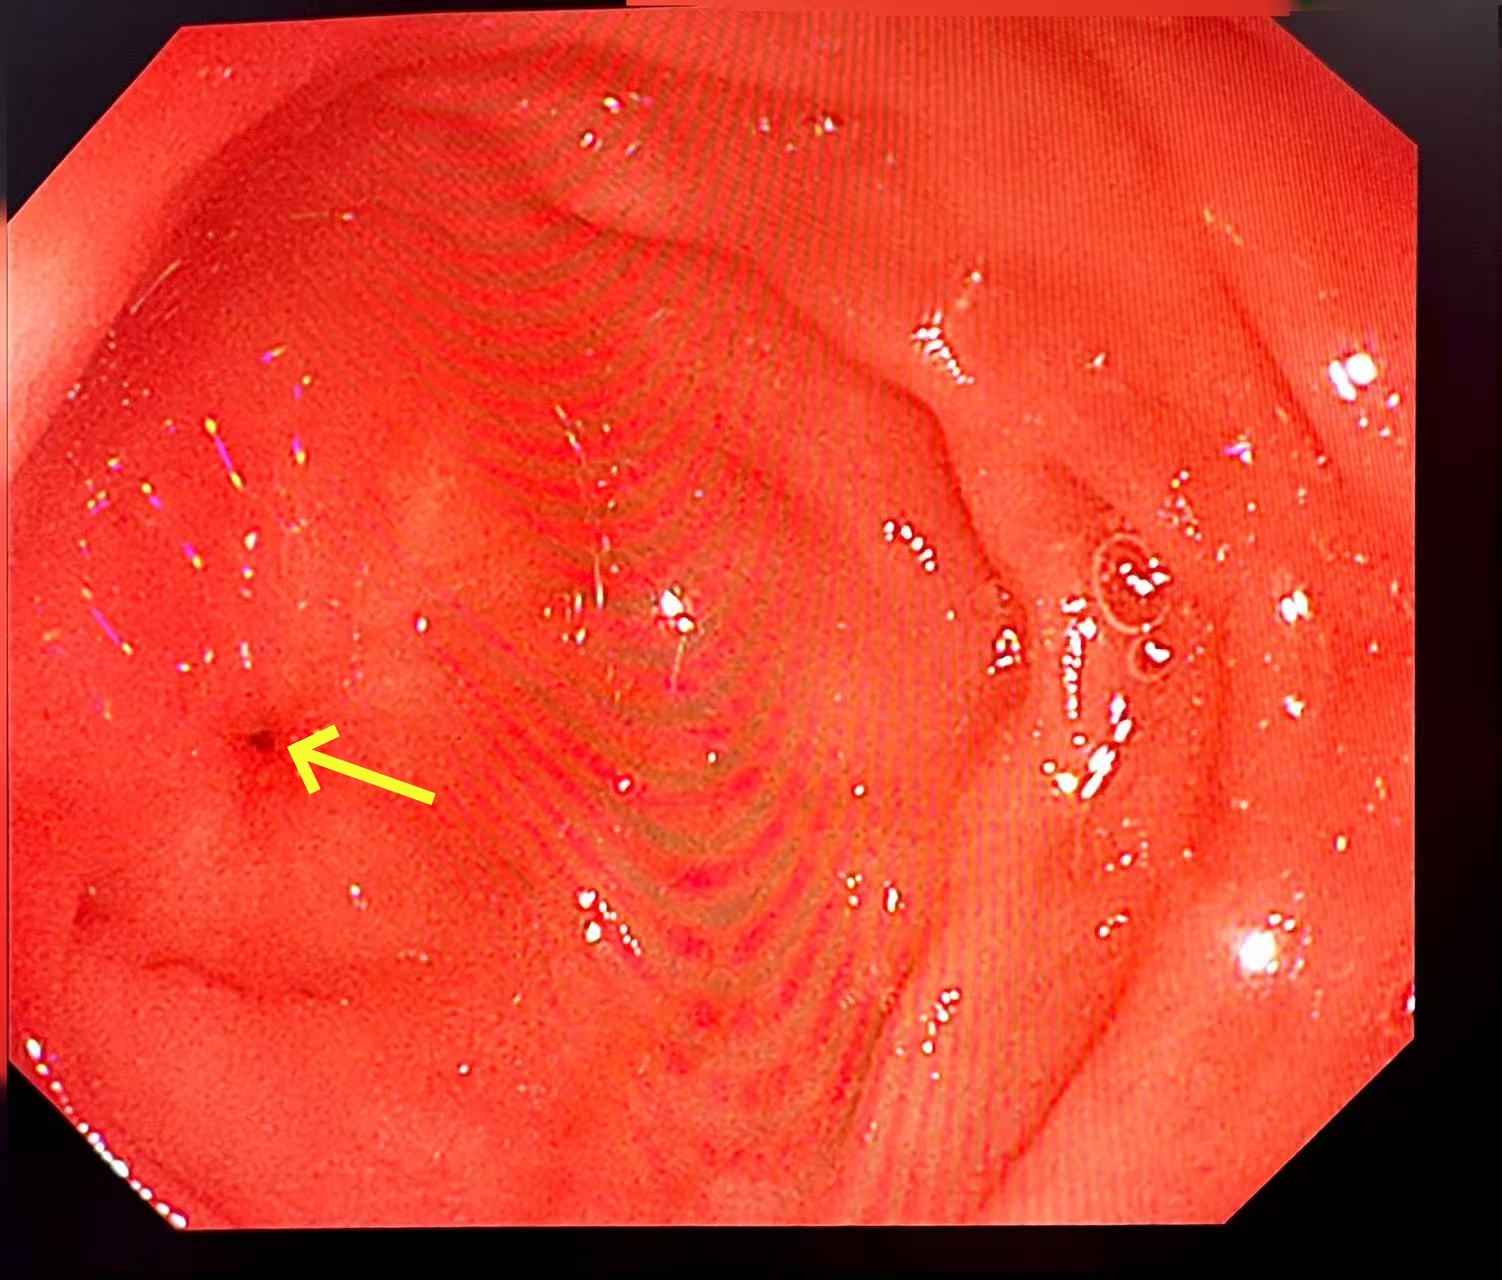

面对疑难病例,医院立即启动多学科会诊(MDT),普通外科(胃肠)联合消化内科、麻醉科、疼痛康复医学科、中医科、心血管内科、骨科、放射科、超声科、临床营养科等多个学科,为患者制定精细诊疗方案。经消化道造影及复查胃镜明确诊断,患者为非甾体抗炎药(NSAIDs)相关胃十二指肠溃疡致十二指肠重度狭窄(最窄处仅容针尖通过),同时继发了肠系膜上动脉综合征及一系列代谢性疾病,治疗难度极大、住院时间长、风险高。

患者肠腔狭窄仅针尖大小(箭头所示),CT亦提示局部结构紊乱不清,基础身体状况较差;无论内镜治疗或外科治疗均存在风险。郑皓医生与患者及家属进行详细病情沟通,患者家属表示积极配合治疗。普通外科(胃肠)及消化内科医疗团队迎难而上,制定个体化救治方案:先后实施2次高风险十二指肠球囊扩张术,配合静脉营养、空肠营养治疗、中医特色治疗,并予以进食后保持俯卧位等护理指导。鉴于患者已行多次CT及消化道造影,主治医师考虑射线辐射等问题,联合超声科为患者行超声造影检查,评估胃动力及胃排空。经过20天昼夜守护,成功规避再喂养综合征、代谢性脑病、误吸等致命并发症,闯过一道道生死关卡。出院时,患者体重较入院时增加3.5kg,胃肠功能完全恢复;出院一周随访,状态持续向好,生活逐步回归正常。三面锦旗,是患者的感恩,更是医者的担当。重庆医科大学附属巴南医院将持续发挥多学科协作优势、精湛诊疗技术与人文关怀,为百姓健康筑牢防线。